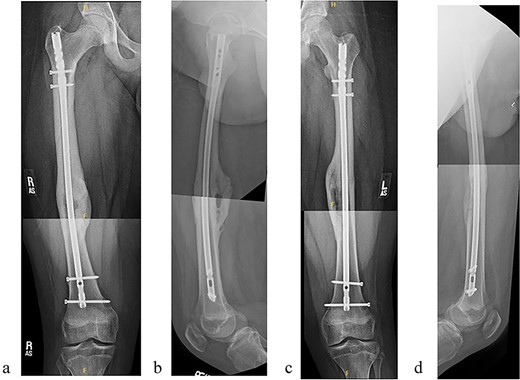

The patient underwent sequential bilateral trochanteric entry antegrade femoral intramedullary rods (Stryker, Kalamazoo, MI, USA) after utilizing bilateral RIAs. We first passed the 8.5-mm end-cutting reamer from the RIA system (DePuy Synthes, Solothurn, Switzerland) and then upsized to an 11.5-mm reamer (Fig. 3a–d). We used the same reamers to prepare the contralateral side.

(a) Obtaining greater trochanteric entry starting point. (b) Fracture reduction with the “F” tool and passed ball-tipped guidewire. (c) Sequentially reaming with the RIA. (d) Maintained fracture reduction with implanted rigid femur rod.

The patient tolerated the procedure well and recovered uneventfully. He was noted to have circumferential osseous healing at 1 year and underwent bilateral femur IMN removal 1.5 years postoperative without complication (Figs 4a–d and 5a–d).

(a) Right femur AP radiograph. (b) Right femur lateral radiograph. (c) Left femur AP radiograph. (d) Left femur lateral radiograph.